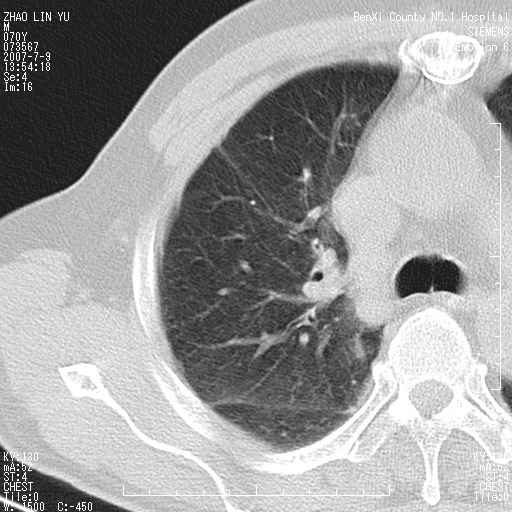

以下是引用王靖旗在2007-7-10 17:12:00的发言:[br] 男、70、咳嗽两个月,半年前换瓣手术,胸片未见异常,于昨天行x片发现右肺上野大片影,行ct扫描,这里是减薄图像,余肺正常。明天晚上会有增强扫描片,到时我会上传。[br][br] 冠状位请大家细看,应该是有意义的,[br][br] 请大家先看平扫发表意见。[br][br]

以下是引用zhangzhongshou在2007-7-10 21:43:00的发言:[br]右肺上叶周围型肺癌,以孤立型细支气管肺泡癌可能性大。